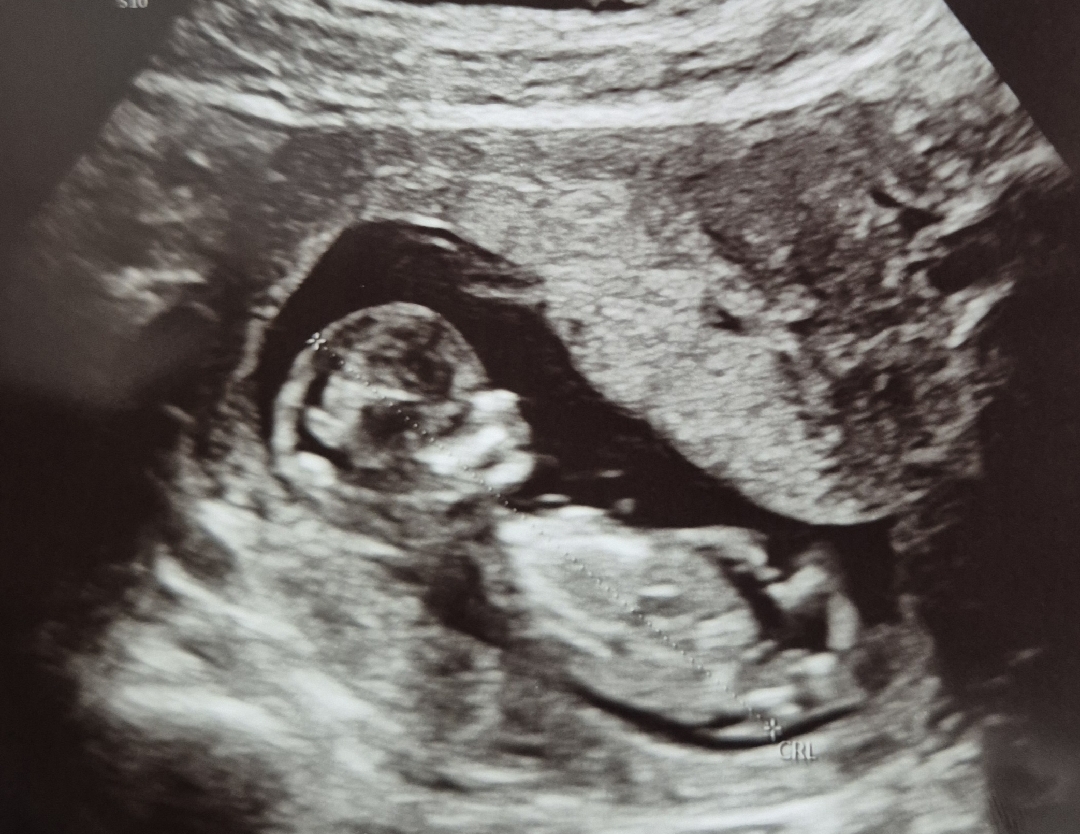

아기가 생식기 돌기를 가리고 있어요.

12주3일 성별 각도법 궁금해요

이 사진으로는 아직 모르는걸까요?